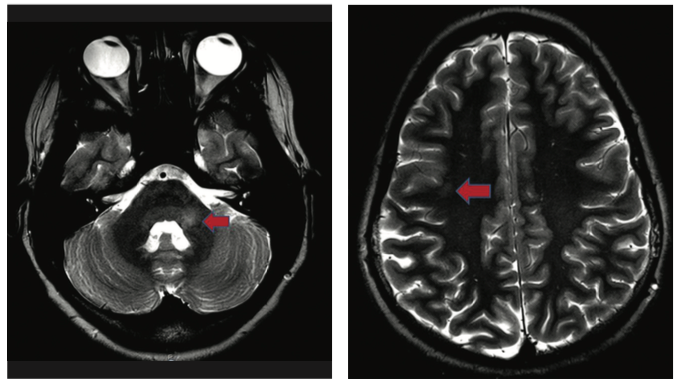

J. Nicholas Brenton, MD; Rachel Gagen, MD

A previously healthy 14-year-old girl presented with a history of subacute onset of double and blurred vision.